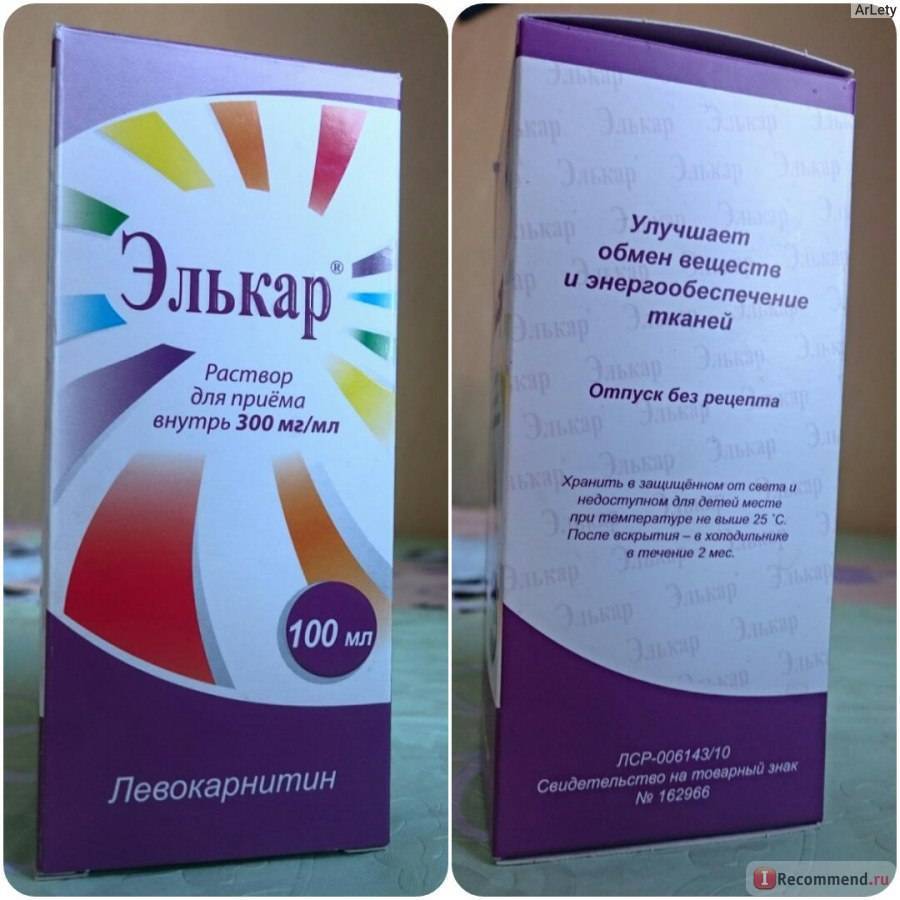

Элькар – это универсальное лекарственное средство, которое входит в комплексные схемы лечения различных нарушений здоровья у взрослых и детей. Он применяется в удобных лекарственных формах (раствор для приема внутрь, сироп и капли для детей, раствор для инъекций). В зависимости от патологии и возраста больного лечащим врачом подбираются индивидуальные схемы лечения с уточнением:

Большое значение имеет соблюдение доз и уточнение % содержания левокарнитина:

20 и 30% раствор для приема внутрь;

10% раствор для инъекций (реже, но все, же в аптечной сети встречается и 50% раствор – 500 мг левокарнитина в 1 мл – на это также необходимо обращать внимание);

30% капли для приема внутрь с удобным дозатором для детей или мерной ложкой или стаканчиком для старших пациентов.

Препарат Элькар содержит L-карнитин (природное вещество) и вспомогательные вещества – сорбиновую кислоту и воду.

Приобретая Элькар в каплях, обратите внимание на инструкцию по приему, особенно, когда это касается детей. Элькар в каплях выпускается в виде 20% раствора и Элькар 30%

Средство традиционно выпускается во флаконах темного стекла объемом от 25 до 100 мл, к которым может прикладываться мерная ложка или мерный стаканчик. С учетом особенностей дозировки, даже самого маленького флакона хватит на полноценный курс для взрослого человека, впрочем, зависит это и от способа применения.

- Активное действующее вещество — карнифин, известный как L-карнитин, вспомогательные компоненты — лимонная кислота, вода.